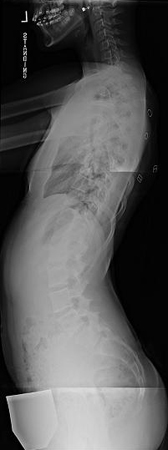

Lateral scoliosis radiograph of a 13-year-old girl with a 49° right thoracic curvature

From the collection of Stuart Weinstein, MD, University of Iowa; used with permission